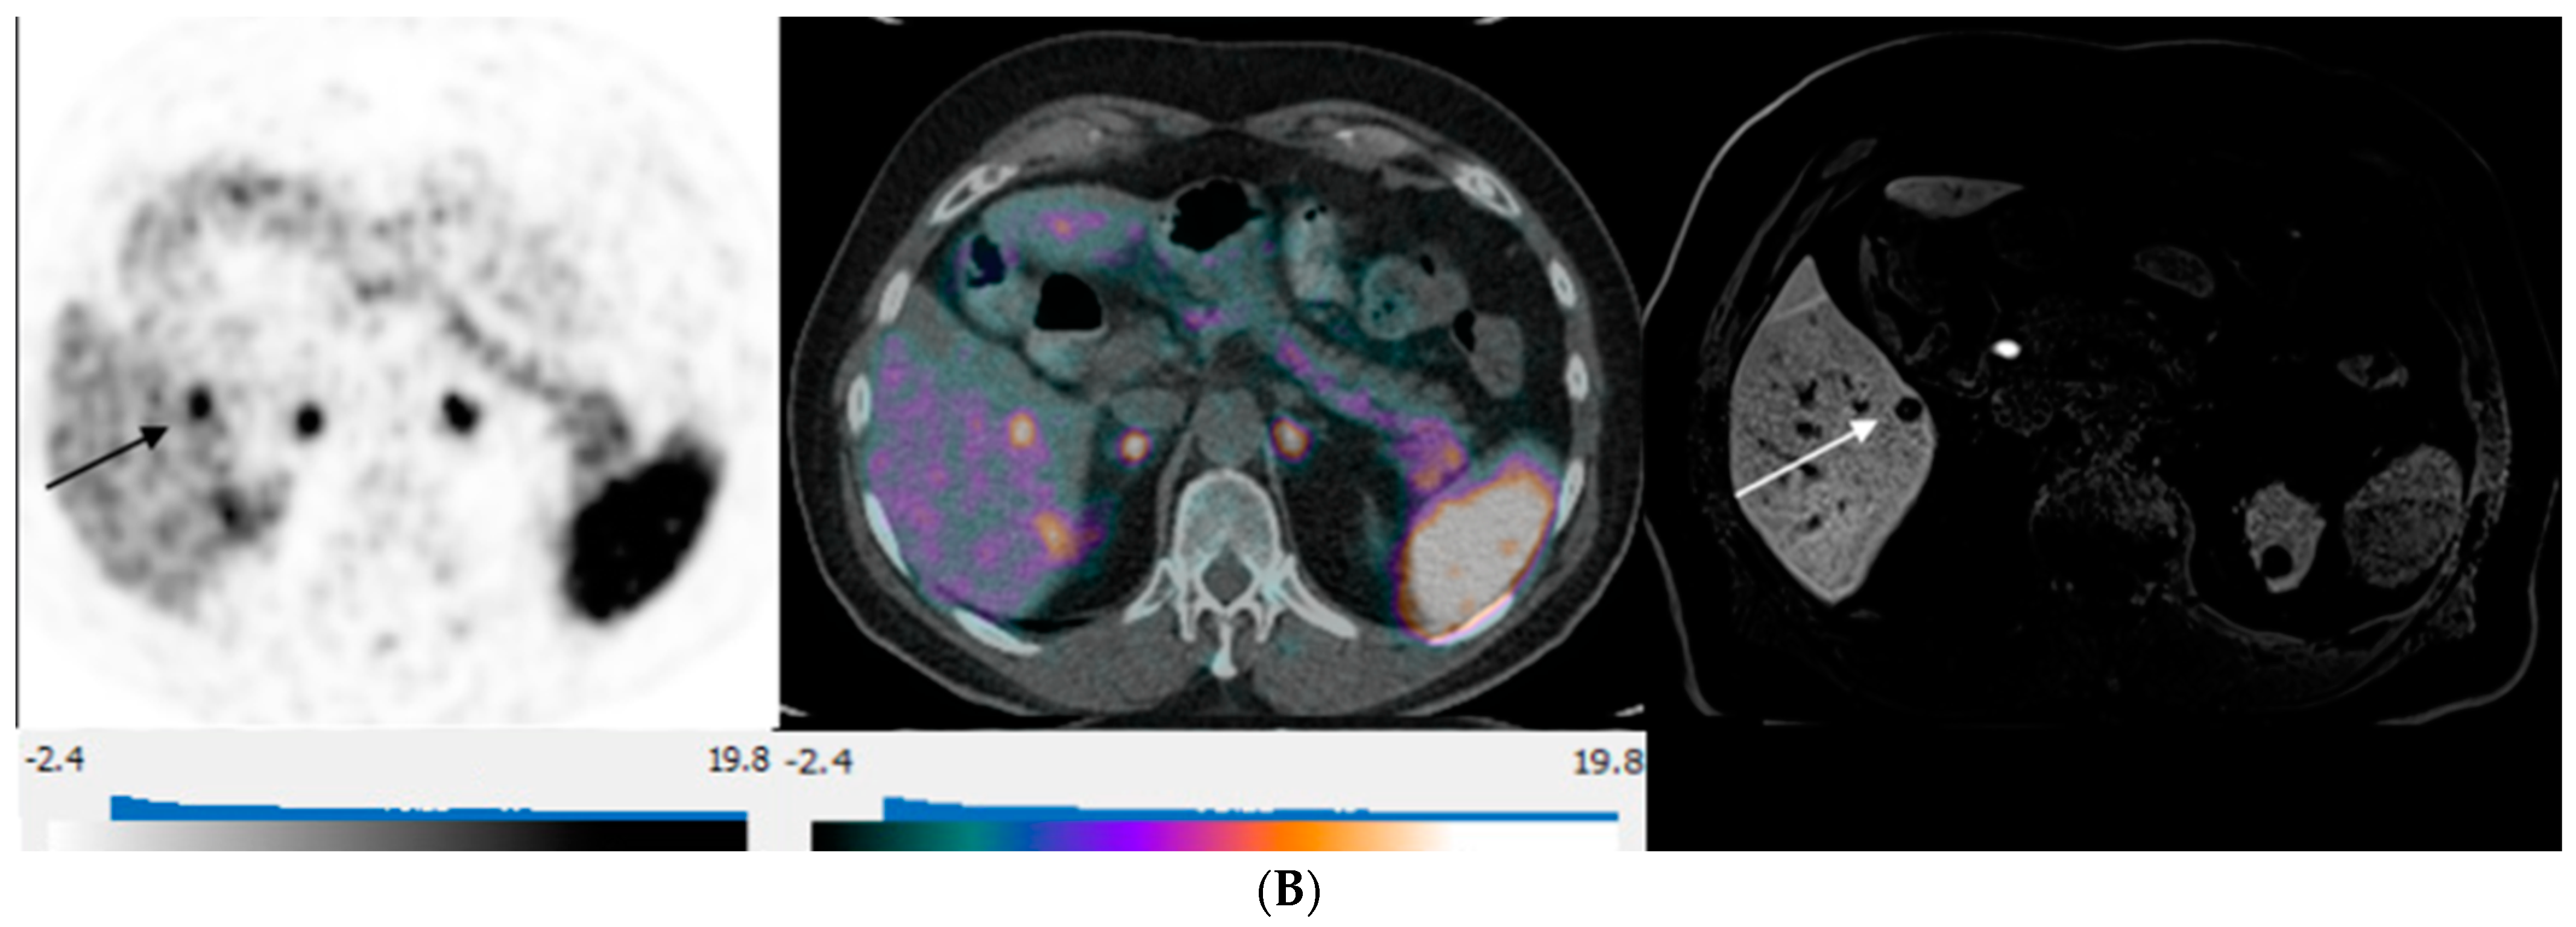

3. Results